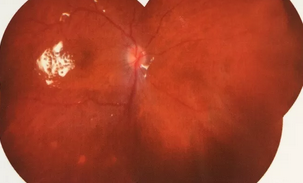

独眼,视网膜全脱离已成窄漏斗状、陈旧性葡萄膜炎、瞳孔后黏连无法散大,且并发白内障使得视网膜周边部细节情况无法看清,左眼已无光感,角膜白斑,瞳孔闭锁,还填充着硅油。右眼既往葡萄膜炎病因不清,一年中发病3、4 次都是用激素医治。左眼多年前是“天那水”溅入后又发生玻璃体出血手术后……令人担心的是这次我们克服重重困难救治全部脱离的视网膜 后,可能会面对长期慢性葡萄膜炎、长期药物医治的继发性高眼压,以及葡萄膜炎的再次复发等,稍有不慎就是不逆性致盲了。

后,终于新旧病变处理完毕,展平复位了即将全部粘连在一起的视网膜,手术获得了 !没有下夜班仍继续在医院组织会诊参加手术的助手龙飘飘医生也长舒了一口气说:挽救了一个眼,挽救了一个人,挽救了一个家庭!